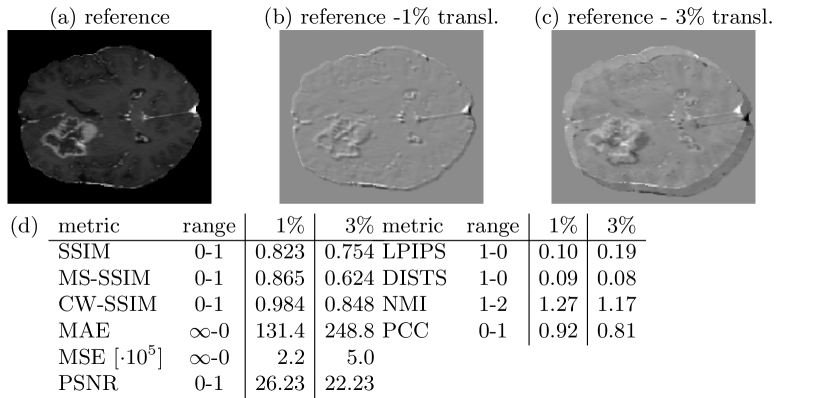

3.2 Pitfall 2: Similarity of Misaligned Images

In image-to-image translation, the source domain input image and the target domain image are often misaligned, because both images were acquired at different timepoints or even with different devices. Therefore, an image synthesized from a misaligned input image is also often misaligned. However, in most cases, medical images are perceived as similar and interpreted in the same way, regardless of small spatial misalignments. Fig. 2 shows that small translations, that are hardly visible, significantly affect most metric scores. Only CW-SSIM and DISTS do not show large changes as they were designed and reported to be less sensitive to misaligments.